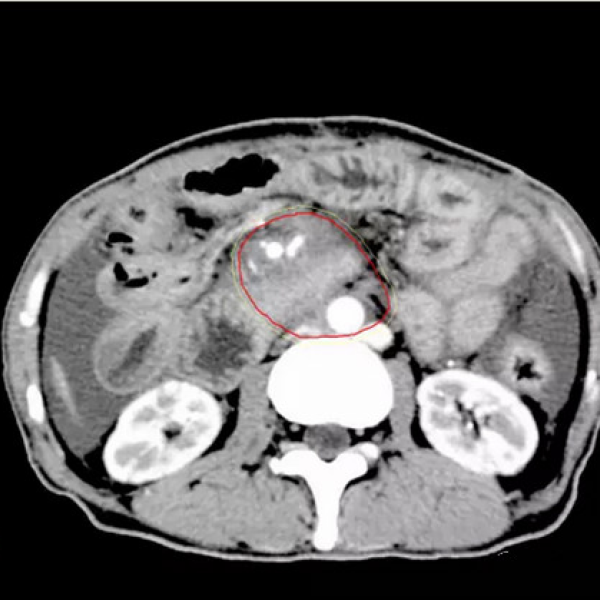

以下为2016-06-16CT定位片: